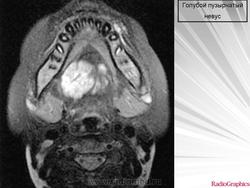

Среди наследственных заболеваний этого типа наиболее редко встречается синдром голубых эластичных (резиновых) пузырчатых невусов (blue rubber bleb nevus syndrome - BRBNS) - редкое сосудистое семейное заболевание, проявляющееся множественными голубыми невусами в виде эластичных пузырчатых бляшек, поражающими кожу и внутренние органы. Описан G.Gascoyen в 1860 г., но в M.W.Bean in 1958 предложил термин, обратив внимание на сочетание с гемангиомами желудочно-кишечного тракта. Связано с нарушением ангиогенеза. С 1966 г. описано более 60 наблюдений (Atten M. et al., 2000).

Голубой пузырчатый невус - редкий синдром, основным проявлением которого служат множественные венозные мальформации кожи, слизистых оболочек, желудочно-кишечного тракта, иногда других внутренних органов. Невусы при этом синдроме образованы скоплением расширенных вен. Могут носить врожденный характер, но чаще появляются в раннем детстве и лишь иногда возникают у взрослых. Поражают не только кожу, но и внутренние органы, в том числе желудочно-кишечный тракт. Встречаются спорадически, хотя описаны случаи аутосомно-доминантного наследования.

Типичные элементы представлены одним или несколькими узелками синюшно-багровой окраски, по консистенции напоминающими резину. Их размеры варьируют от нескольких миллиметров до нескольких сантиметров, лишь иногда достигая 5 см. Морщинистая поверхность придает им сходство с соском. Они могут встречаться практически на любом участке кожи, а также на слизистой болочке губ, рта и головки полового члена. Иногда они залегают довольно глубоко в коже, проявляясь лишь в виде участка голубоватой окраски. Обычно для них характерна спонтанная болезненность, особенно по ночам. Иногда этот признак отсутствует до начала пубертатного периода или вообще не отмечается. Если ангиоматозные сосуды невуса оказываются интимно связанными с потовыми железами, то кожа, покрывающая невус, приобретает выраженную потливость. При синдроме голубого пузырчатого невуса аналогичные венозные мальформации встречаются в желудочно-кишечном тракте, где могут кровоточить, на языке и под языком, а также поражают носоглотку, легкие, сердце, печень, селезенку, мозг оболочки мозга, мочеполовой тракт, мышцы и суставы. Иногда отмечаются различные костно-мышечные аномалии.

Гистологически голубой пузырчатый невус проявляются крупными, наполненными кровью просветами вен, располагающимися в дерме и подкожной жировой клетчатке. Поверхностно расположенные просветы часто очерчены только эндотелиальными клетками, глубже расположенные просветы имеют более развитую сосудистую стенку с гладкими мышцами. Сосудистые каналы разделены между собой прослойками соединительной ткани. Невусы в желудочно-кишечном тракте сформированы из сосудистых каналов, гистологически сходных с наблюдаемыми в собственной пластинке слизистой оболочки и в подслизистом слое.

Спонтанной инволюции кожных и висцеральных очагов поражения голубого пузырчатого невуса не бывает. Повторные желудочно-кишечные кровотечения могут привести к выраженной анемии.

Дифференциальный диагноз голубого пузырчатого невуса проводится с множественными ангиоматозными невусами, эккринным ангиоматозом, гамартомами, гло-мангиомами, синдромом Маффуччи, диффузными ангиокератомами туловища.

Лечение голубого пузырчатого невуса, как правило, симптоматическое. Эффективно удаление с помощью лучей углекислотного лазера. Паллиативным методом лечения является резекция вовлеченного в процесс отдела кишечника.